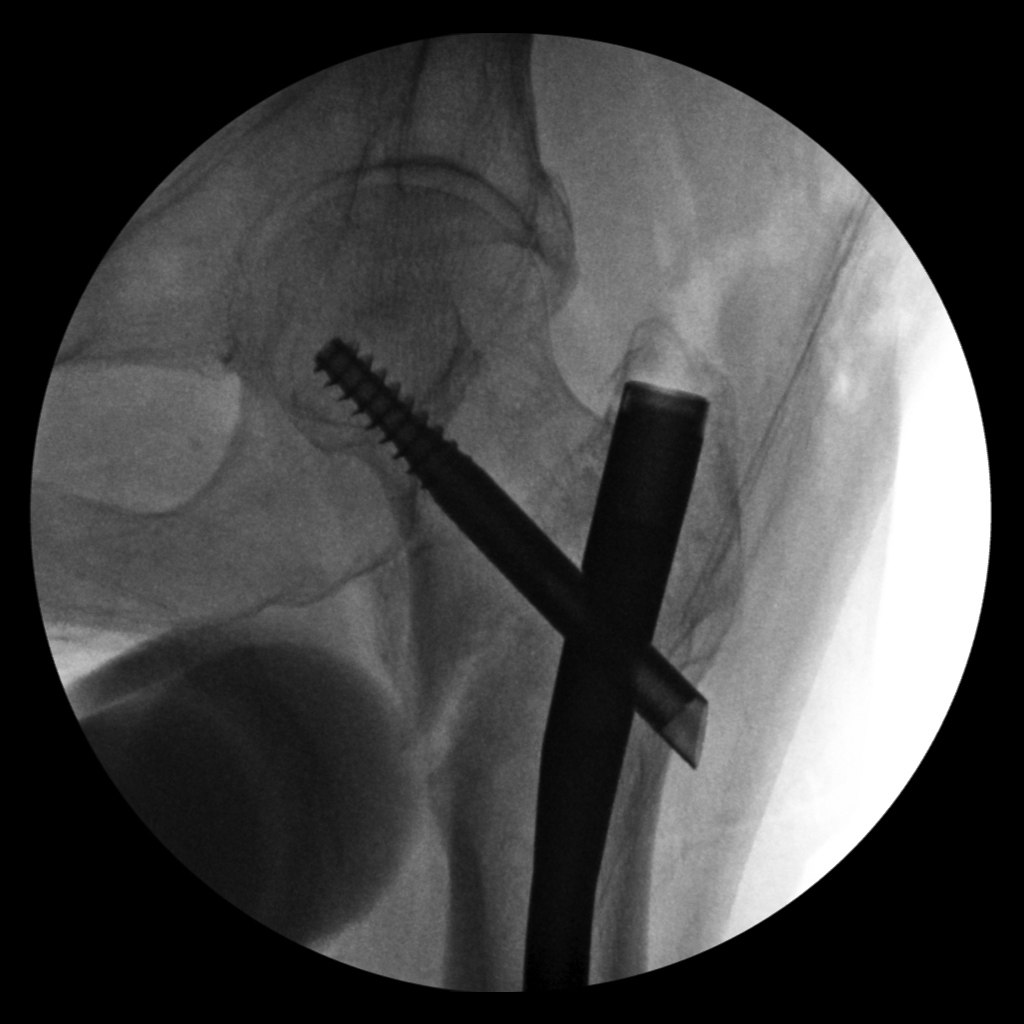

Intraoperative fixation of an intertrochanteric fracture demonstrates a cephalomedullary device with the tip of the cephalic screw positioned too short and very inferior in the neck (very large tip-apex distance). |

Subsequent fracture fixation failure observed as the head and neck segment of the femur flexed 90 degrees with cut-out of the screw approaching the hip joint. |